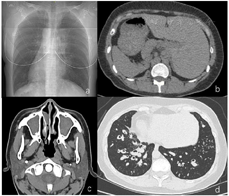

经鼻呼气一氧化氮:8bbp。肺功能提示中度阻塞性通气功能障碍,呼气峰流速下降,弥散功能正常。肺CT:内脏完全转位,双肺弥漫分布微结节,多发囊状扩张支气管,双肺下叶支气管管腔内可见高密度影填充,左肺中叶体积缩小,成三角形高密度影,2009年肺CT与2020年肺CT比较可见支气管扩张明显加重(图1)。鼻窦CT提示双侧上颌窦、筛窦、额窦、蝶窦内见密度增高影,慢性鼻炎(图2)。鼻内镜可见右侧中鼻道息肉组织。支气管镜检查可见主气道大量黏性分泌物,取支气管黏膜组织刷检送电镜检测可见部分纤毛外动力臂缺失及复合纤毛(图3)。高速视频显微镜下观察纤毛摆动频率减慢。采集全血标本,提取基因组DNA进行外显子基因检测,结果发现DHAH5基因63号外显子出现一个杂合突变,在10616号核苷酸由鸟嘌呤G变为腺嘌呤A(c.G10616A)的突变(箭头所示),导致第3539号氨基酸由精氨酸变为组氨酸(p.R3539H),见图4。该位点为国外已报道位点[7]。

患者中年女性,病程较长,表现为反复咳嗽咳痰。CT影像学检查可见内脏完全转位(右位心,左侧肝脏),双肺弥漫分布微结节,多发囊状扩张支气管。鼻窦炎,鼻道息肉。结合中耳炎,嗅觉丧失的病史,以及电镜检查发现气道纤毛超微结构异常,高速视频显微镜发现纤毛摆动频率低,可以明确诊断为Kartagener综合征(完全型Kartagener综合征影像检查见图3)。一般认为Kartagener综合征纯合或复合杂合的双等位基因突变致病,该患者全外显子基因检测发现单杂合基因突变,是否为致病基因尚无法判断。

Kartagener综合征属于PCD的一种亚型,研究发现Kartagener综合征约占PCD的50%,推测发生内脏转位是在胚胎发育中由于胚节纤毛功能障碍,使内脏出现转位或不转位的随机事件[8,9]。Kartagener综合征并不会在出生时即会表现所有临床症状,而是随着年龄增长,患者复发发生慢性咳嗽和呼吸道感染,临床症状逐渐典型。对于表现为完全型Kartagener综合征的患者(同时出现鼻窦炎、支气管扩张、内脏转位三联征),诊断相对容易,但确诊时间往往延迟。而不伴有内脏转位的PCD临床异质性较大,加之临床医生认识水平不足,极易出现漏诊和诊断延误[10],很多患者确诊时已进展至终末状态,早期确诊原发性纤毛运动障碍,尽早开始健康指导及肺康复锻炼对于改善患者预后极为重要。本例Kartagener综合征患者在年幼时常出现反复咳嗽咳痰症状,直至中年确诊。目前国内缺乏Kartagener综合征长期随访的肺功能及影像学数据,本研究首次对比了患者前后11年随访的肺CT变化,更直观地展示出疾病的进展的过程,特征的肺部病变影像为弥漫性分布,双下肺为主的囊性支气管扩张及粘液栓形成(图1ab)。